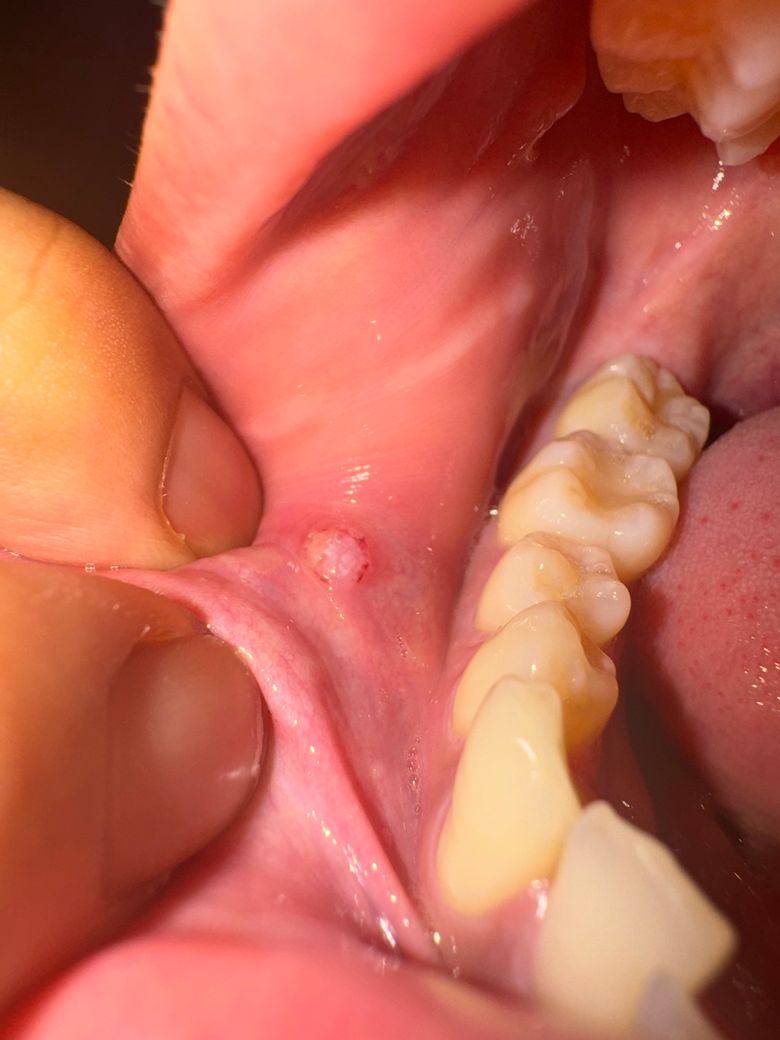

그래서 어제 치과에 갔더니 의사선생님이 니들같은 걸로 뚫으려고하셨는지는 모르겠지만 점막 안에 있다고 피고름만 빼고 안에 소독했다. 약 줄테니 먹어보고 1-2주 뒤에 다시 와서 안사라져있으면 대학병원가봐야한다고하시더라구요…

이건 지금 사진입니다. 선생님들이 보시기에 악성병소일 확률이 높아보이시나요…? 처음엔 그냥 물집이길래 스트레스랑 잠못자서 면역력이 약해져서 생겼나보다하고 별 걱정안했는데 어제 병원가서 직접 이야기 들으니 온몸이 떨리네요… 구강암을 확률이 높아보이나요? 아니라면 어떤 것을 수 있을까요?

• 2번 째 사진

사진만으로는 판별하기 어렵지만 악성병소 가능성은 낮아보입니다. 대학병원에서 조직검사 하는 것이 가장 정확합니다.

구강암은 아니고 낭종같은 거니 치과에 가셔서 마취후에 제거를 해달라고 하시면될것같습니다.